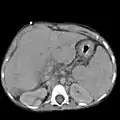

Abdominal CT, showing Morison's pouch as the dark margin surrounding the right kidney (at lower left corner of image).